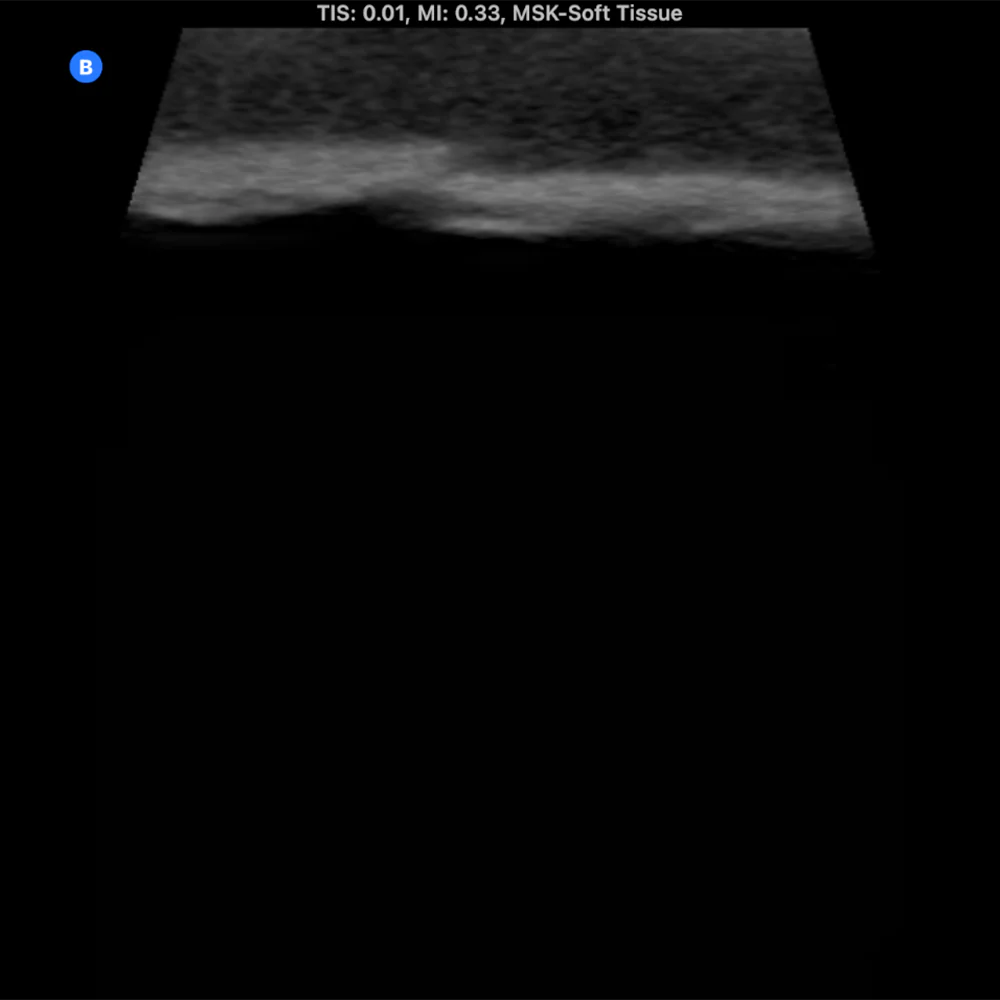

The Bone Fracture Ultrasound Phantom is an excellent training aid for developing the skills needed to identify bone fractures within soft tissue.

- Five bones incorporated within the model (three positioned superficially and two at a deeper level).

- One healthy bone with no fracture, plus four bones featuring fractures of varying severity.

- Produces outstanding ultrasound image quality.